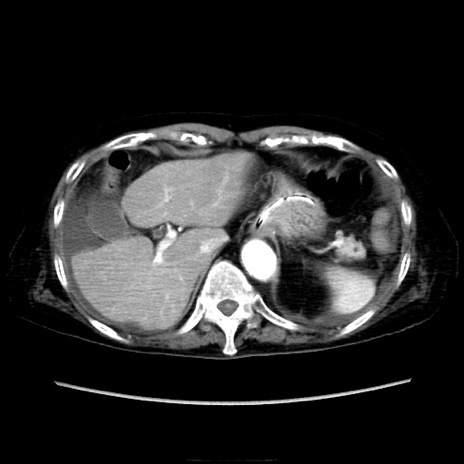

症例40(横断像)

【症例】90歳代女性

【主訴】腹痛・嘔吐

【現病歴】 食欲低下、嘔吐があり昨日他院受診。肺炎と診断され入院となる。入院後より腹部全体に圧痛あり。胃管留置され経過みていたが、症状持続するため、

当院転院となる。

【身体所見】腹部:中央に激痛あり、圧痛あり、反跳痛不明

【データ】WBC 17100、CRP 18.82

横断像